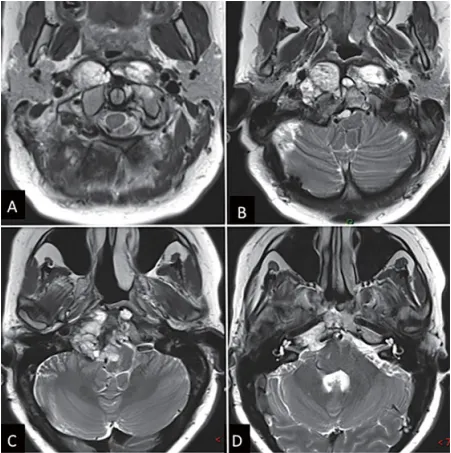

图1:内镜下鼻内镜入路前的术前影像。(A-D)MRI T2 WI显示一个较大脊索瘤延伸至椎前间隙和齿状突周围。肿瘤横向延伸至舌下管和颈静脉孔,并向内侧延伸至硬膜内间隙。肿瘤从斜坡中部延伸至枢椎齿状突周围。